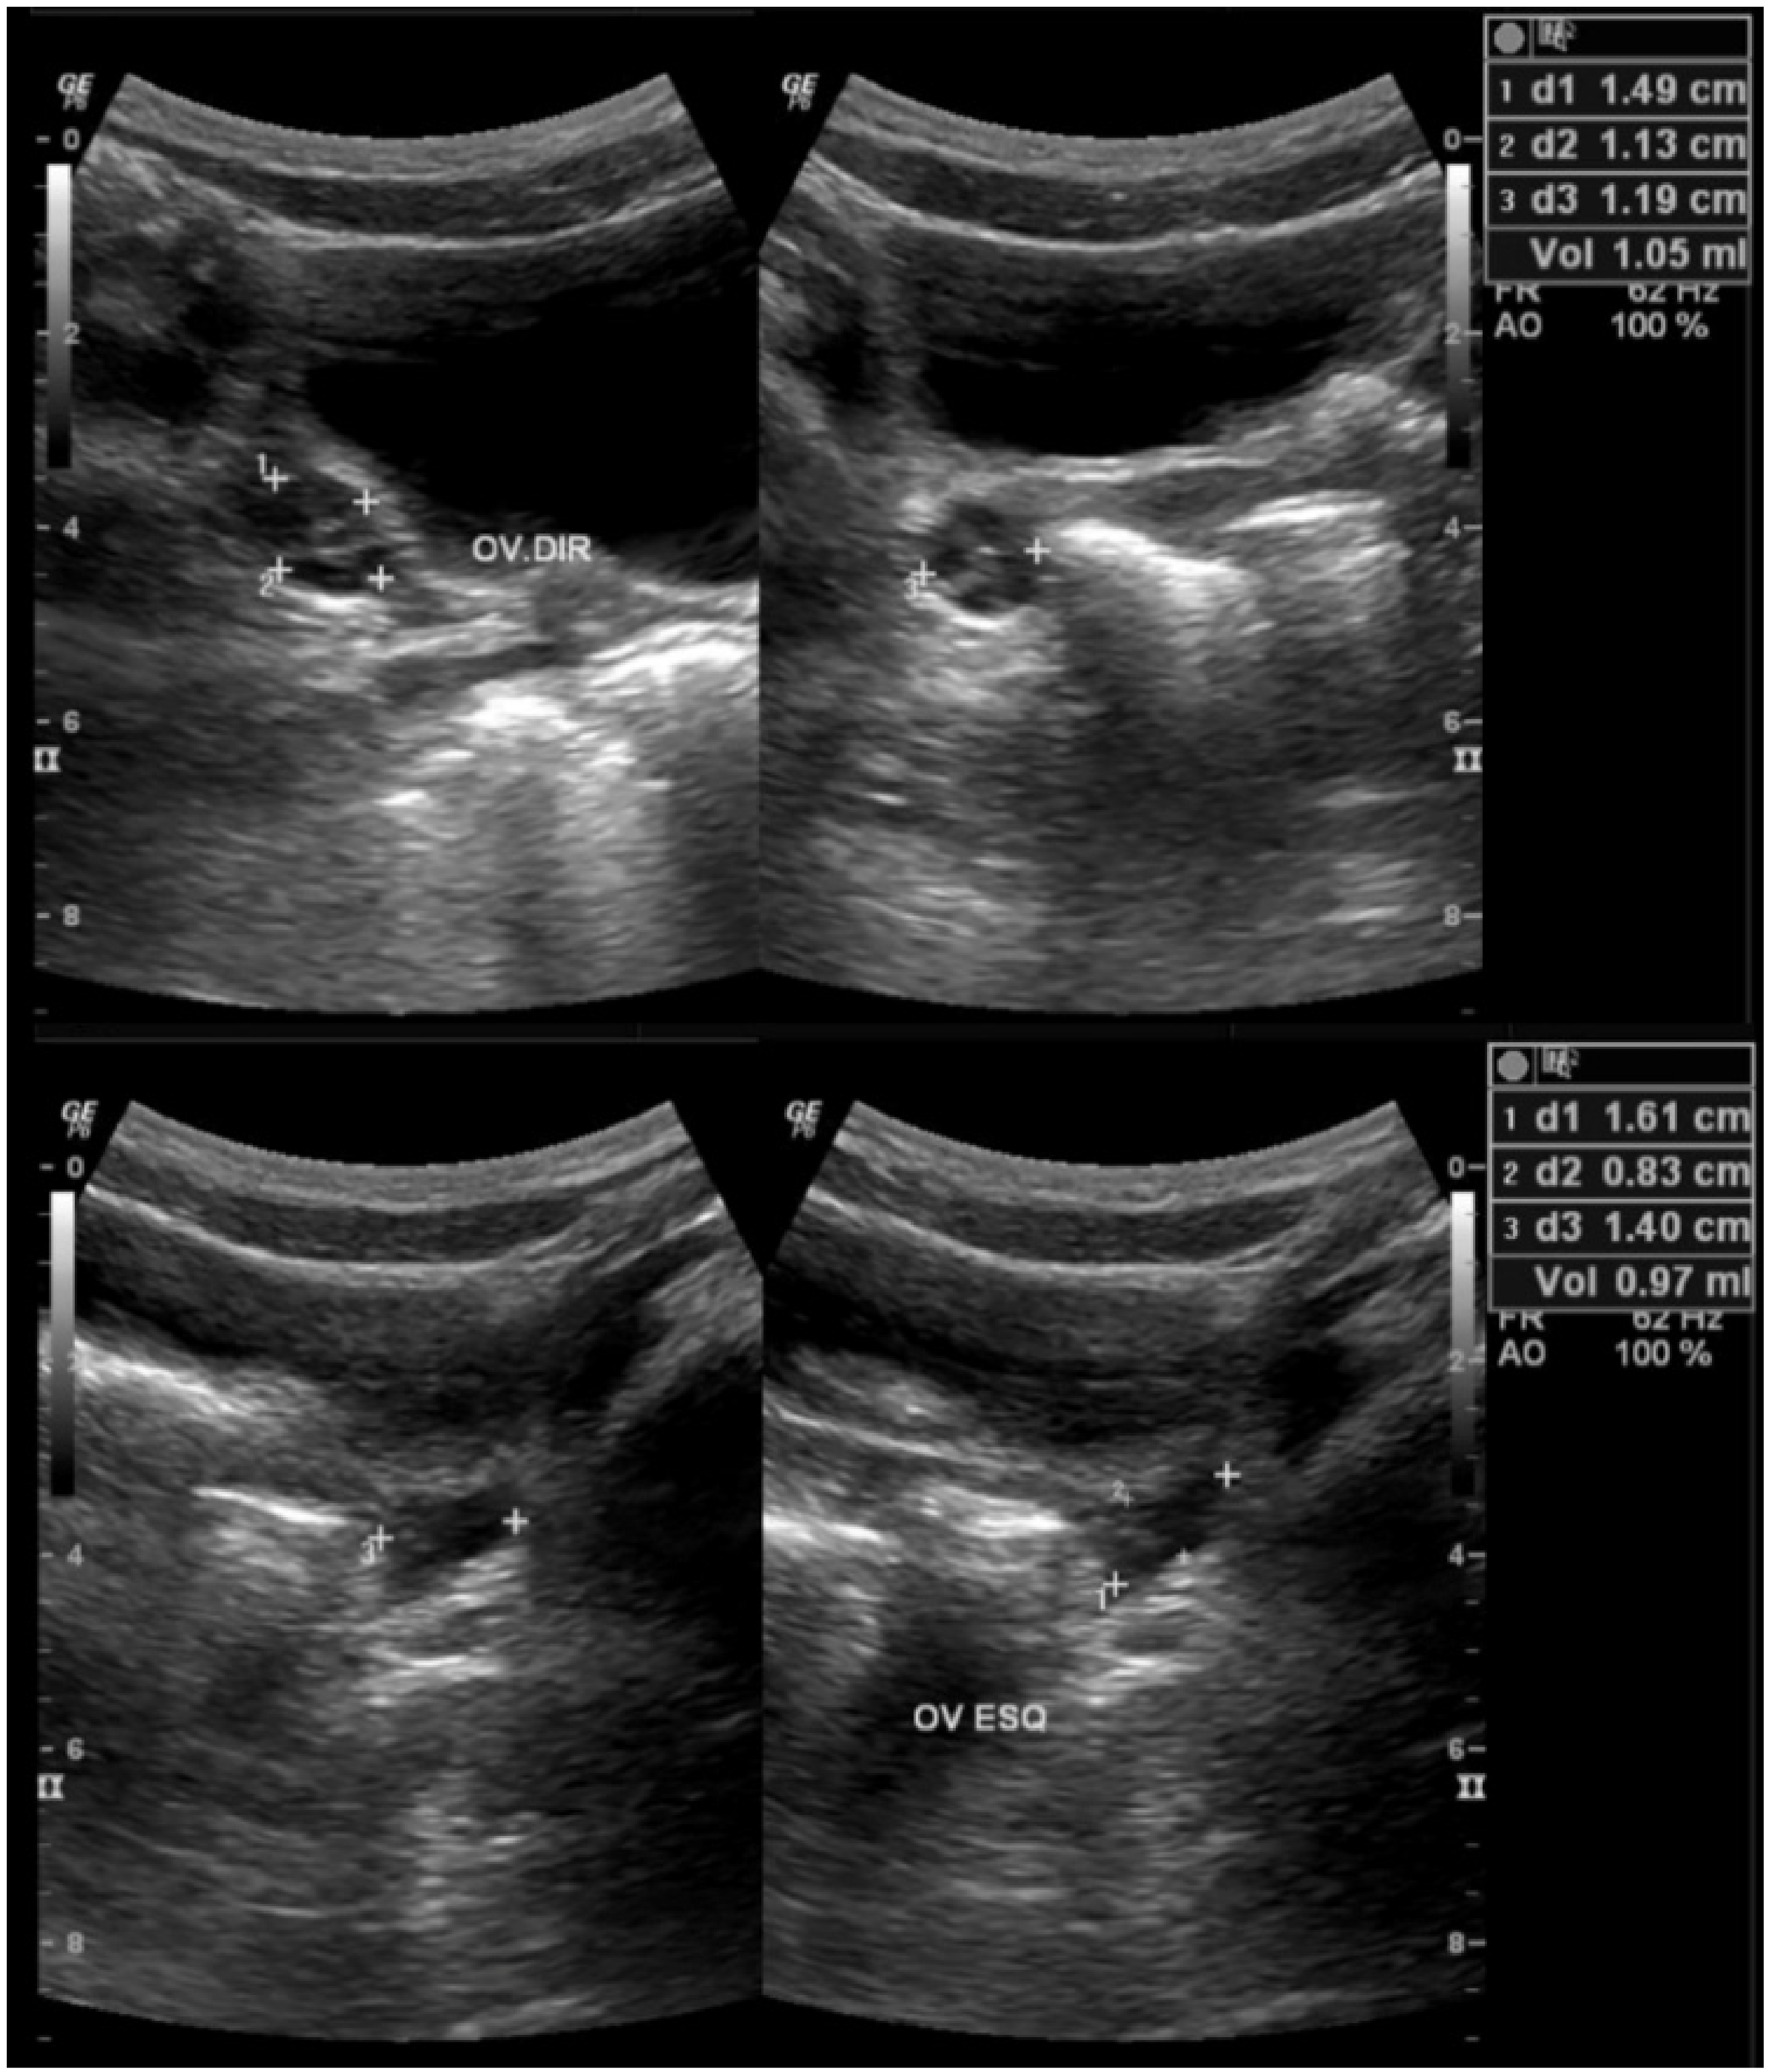

| Ovarian Volume (mL) | |||

| Mean ± SD | 3.15 ± 2.31 | 1.88 ± 0.95 | 0.01 M |